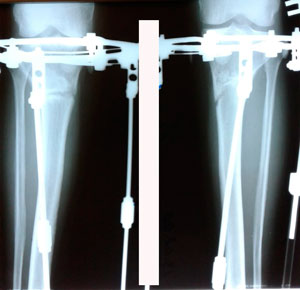

рентген в 90 дней.

IMG_8309-17-01-20-05-34.JPG

IMG_8308-17-01-20-05-34.JPG

Дата операции - 17.10.2019г

Дата снятия аппаратов - 14.02.2020

Срок сращения - 117 дней.